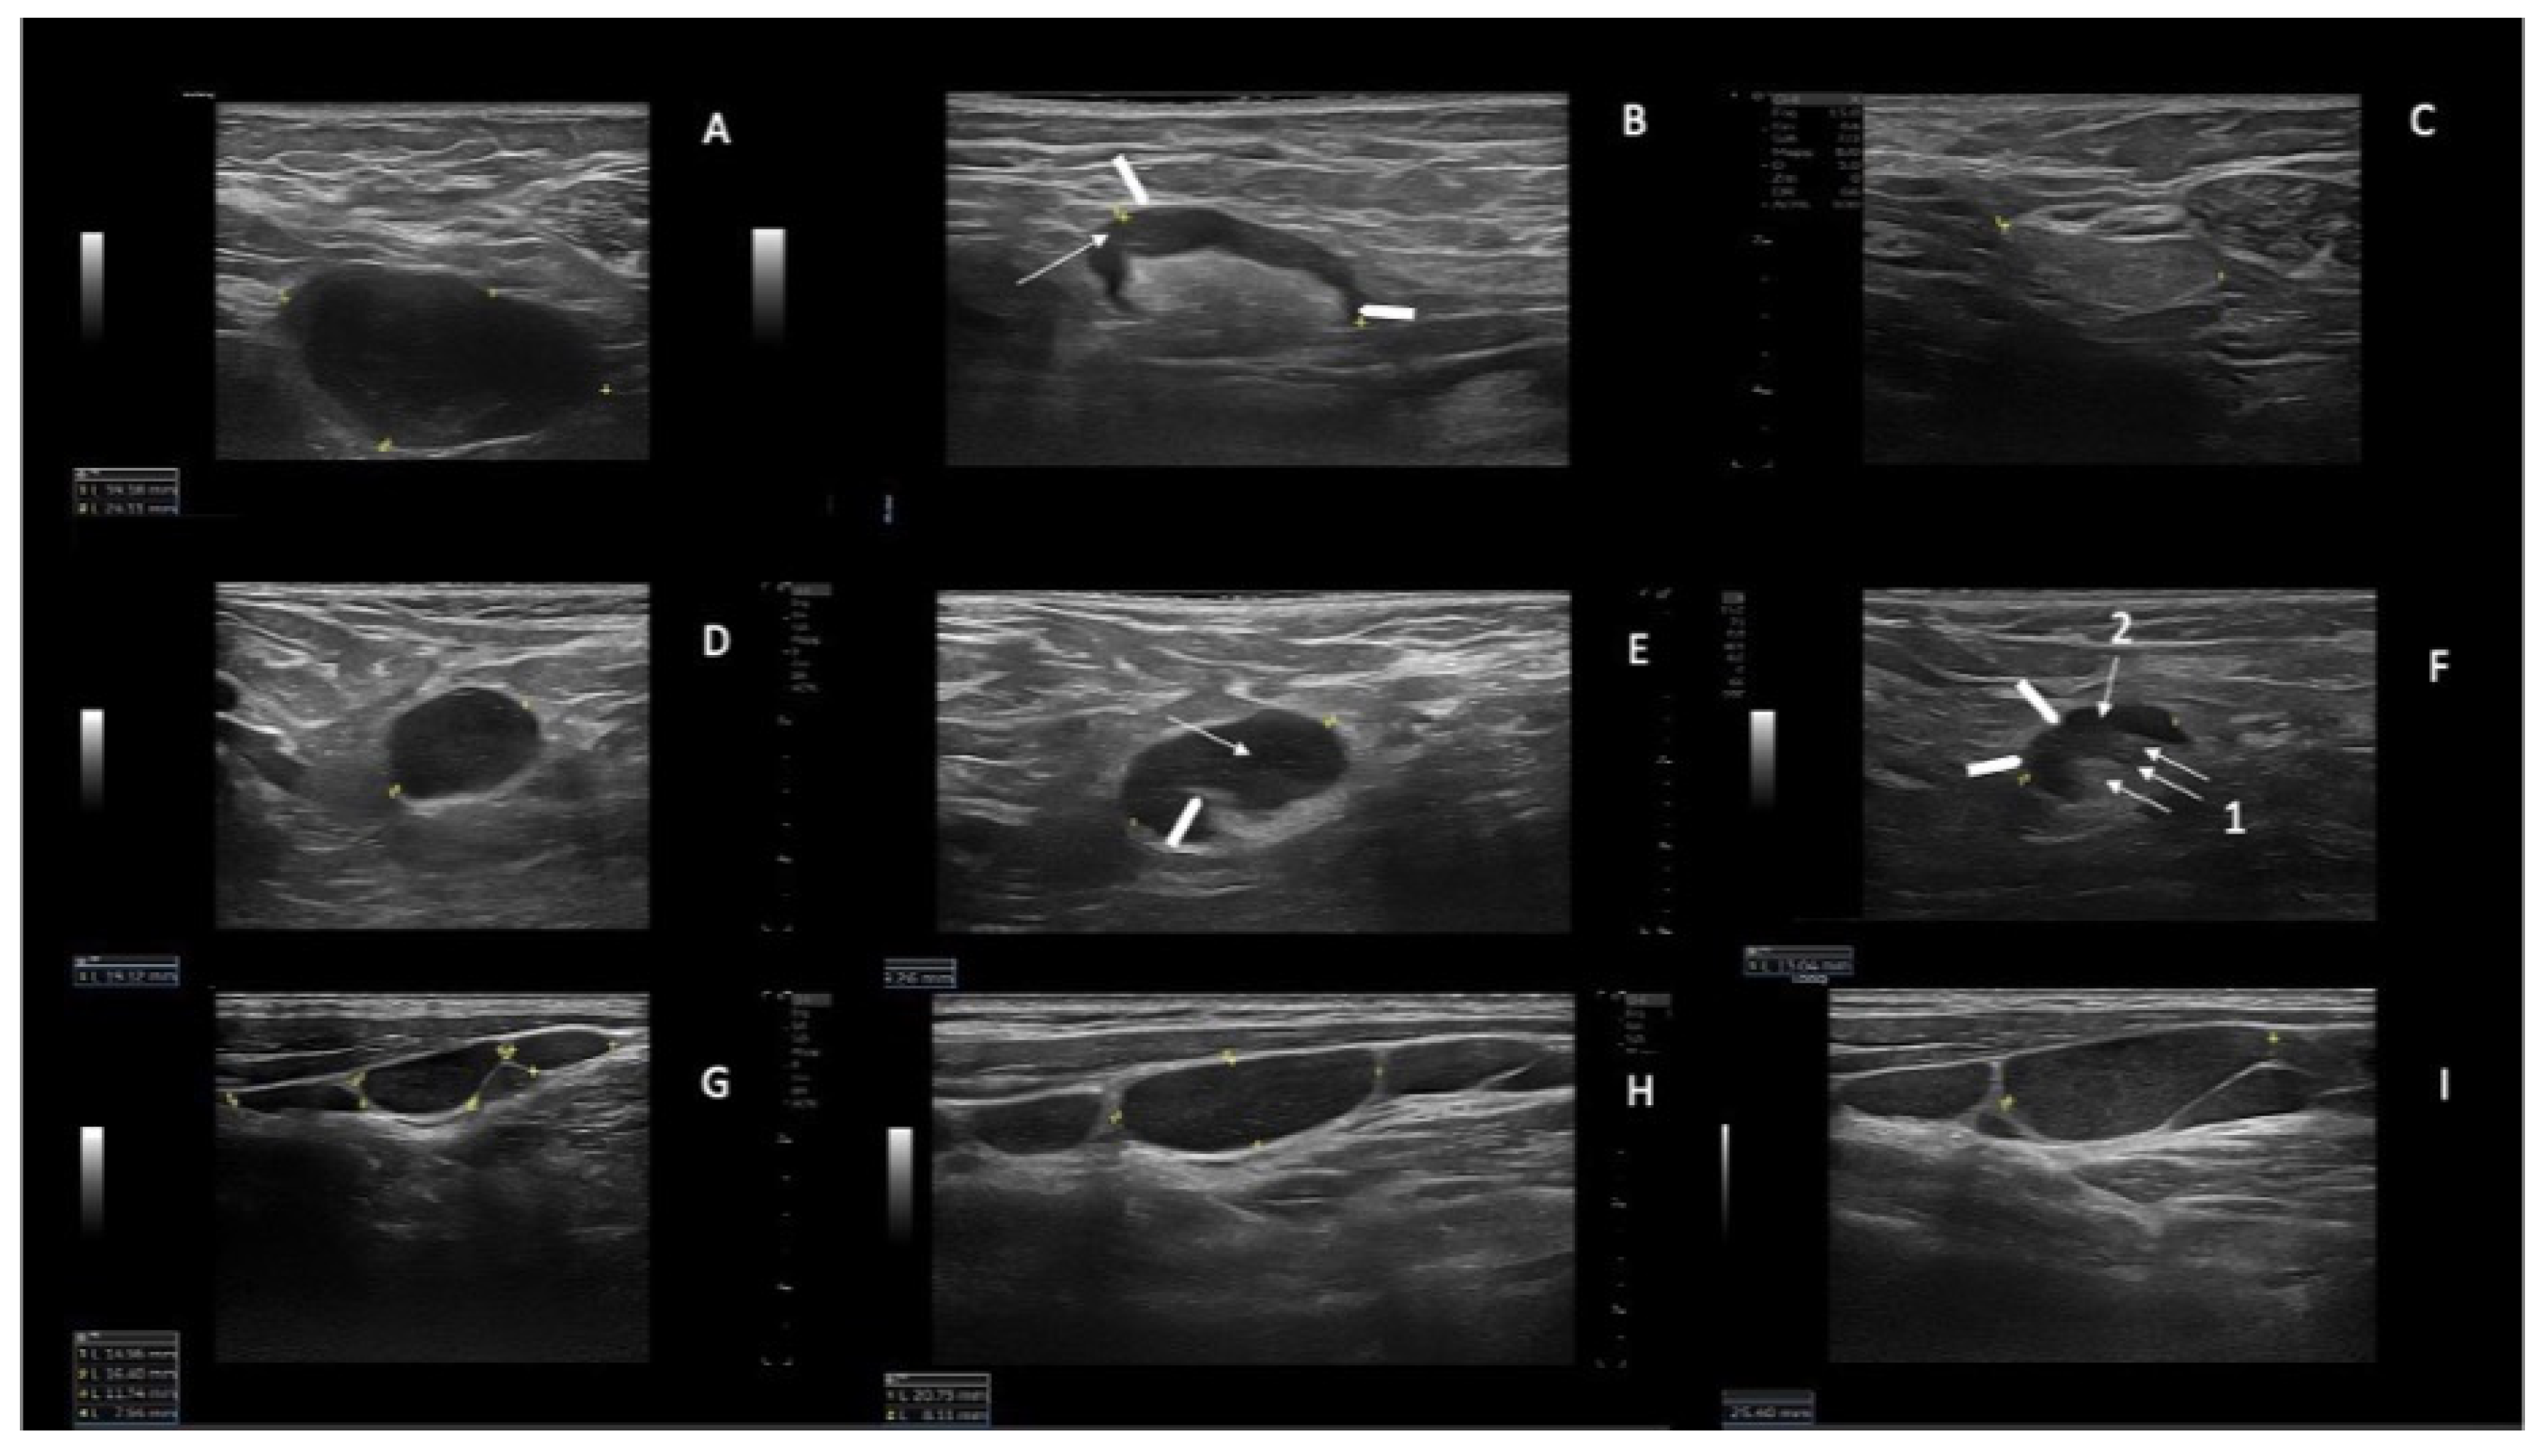

3.5. Lymphnodes Dimensions and Response

3.7. Additional Observations